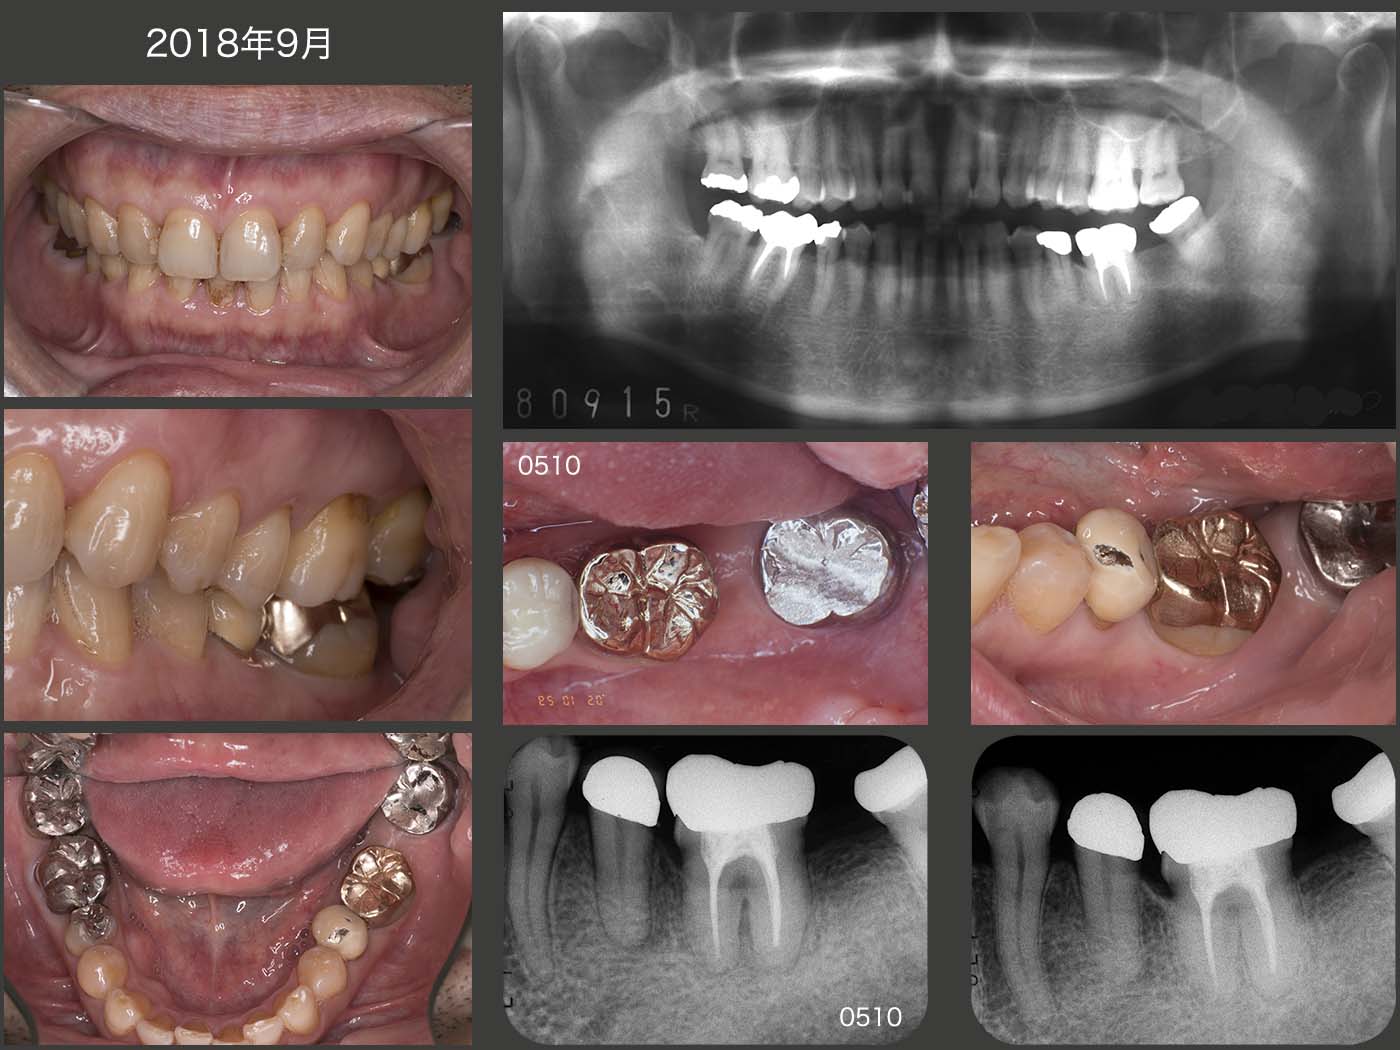

2018年9月の状態.この13年の間に,左下5メタルボンド冠の咬合面の破損修理,および歯科矯正後の後戻りのために左下5,6間のコンタクトの付与を何回か行った.なお左下5は,仮着しておいたため後の修正・修理が可能である.

患者さんは,ストレスが溜まる?と右側上下大臼歯の自発痛が生じる.しかし大概,力が原因で暫くすると自然に治癒することを繰り返してきた.ところが20年2月,また痛みがあるということで来院したが,右下7の遠心に大きなう蝕が見つかった.以前のリコールの時,完全に見逃していた.AIPCで何とか歯髄の保存に努め,10月にクラウンを装着することができた.

移植歯自体は,まったく変化がなく経過良好である.移植歯が偏咀嚼主機能歯でないことが一番の理由かと思われる.